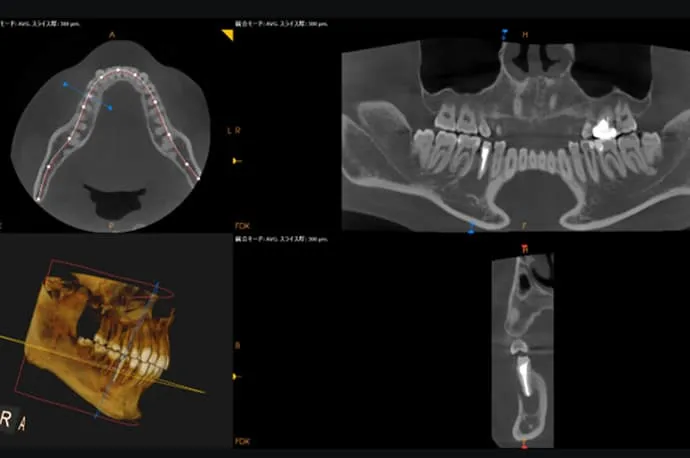

根尖部(根の先)の化膿の診断

歯の根の先が化膿しているかどうかの診断は、歯髄の診断と比べると比較的行いやすく、主にレントゲン検査を用いて確認します。

当院では、すべての患者さまにCT撮影を無料で実施しています。これにより、まだ痛みが出ていない段階の化膿や、通常のレントゲンでは見つけにくい小さな病変まで確認することが可能です。